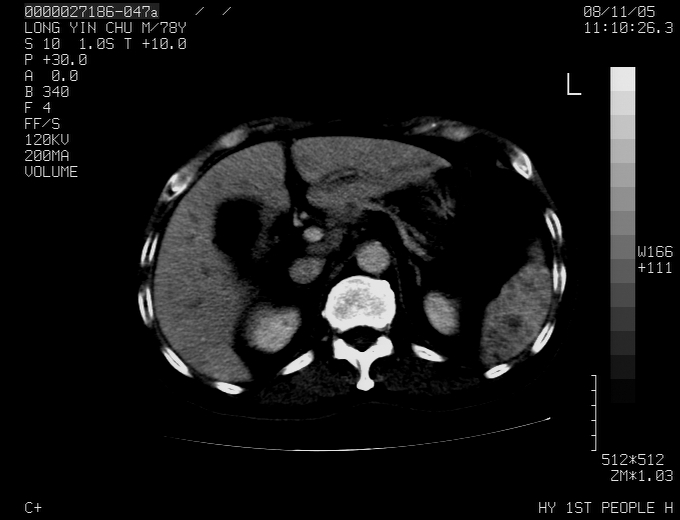

标题: CT16532:M78Y,肝脏病变,请会诊 [打印本页]

标题: CT16532:M78Y,肝脏病变,请会诊

腹胀,腹痛就诊,男性,78岁,外院b超未见异常。

肝ca,脾肾转移

支持脾肾转移瘤,双侧胸腔积液。

考虑弥漫性肝癌并脾及双肾转移.双侧胸水.

图片质量欠佳:多考虑:左侧肾癌。脾脏转移!胸膜转移!

肝脾肾转移瘤可能性大,左肾不除外梗塞,双侧胸水

考虑弥漫性肝癌并脾及双肾转移,双侧胸水。

考虑肝癌并双肾及脾脏转移;双侧胸腔积液。